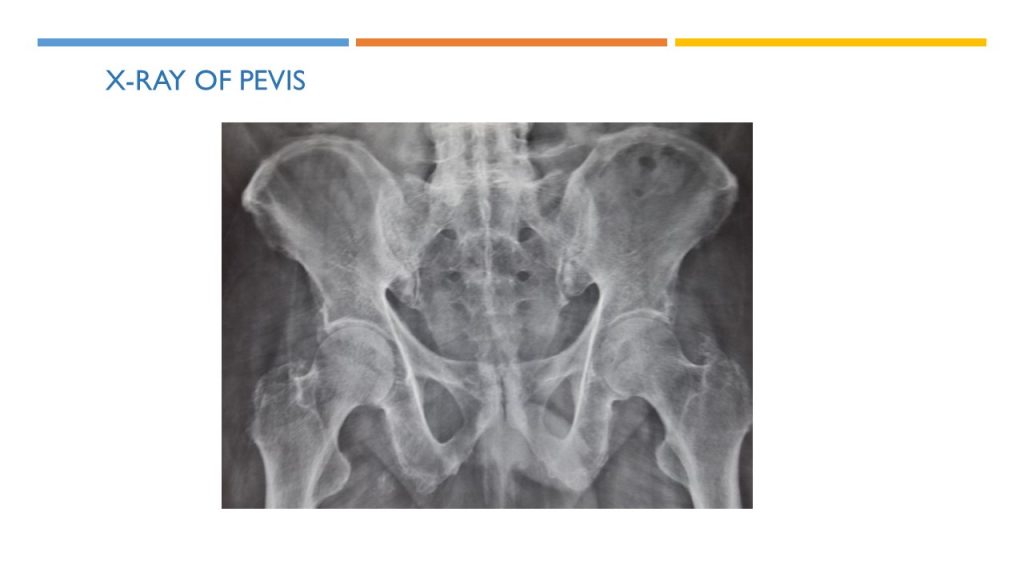

X-RAY OF PEVIS

X-ray of pelvis indicates